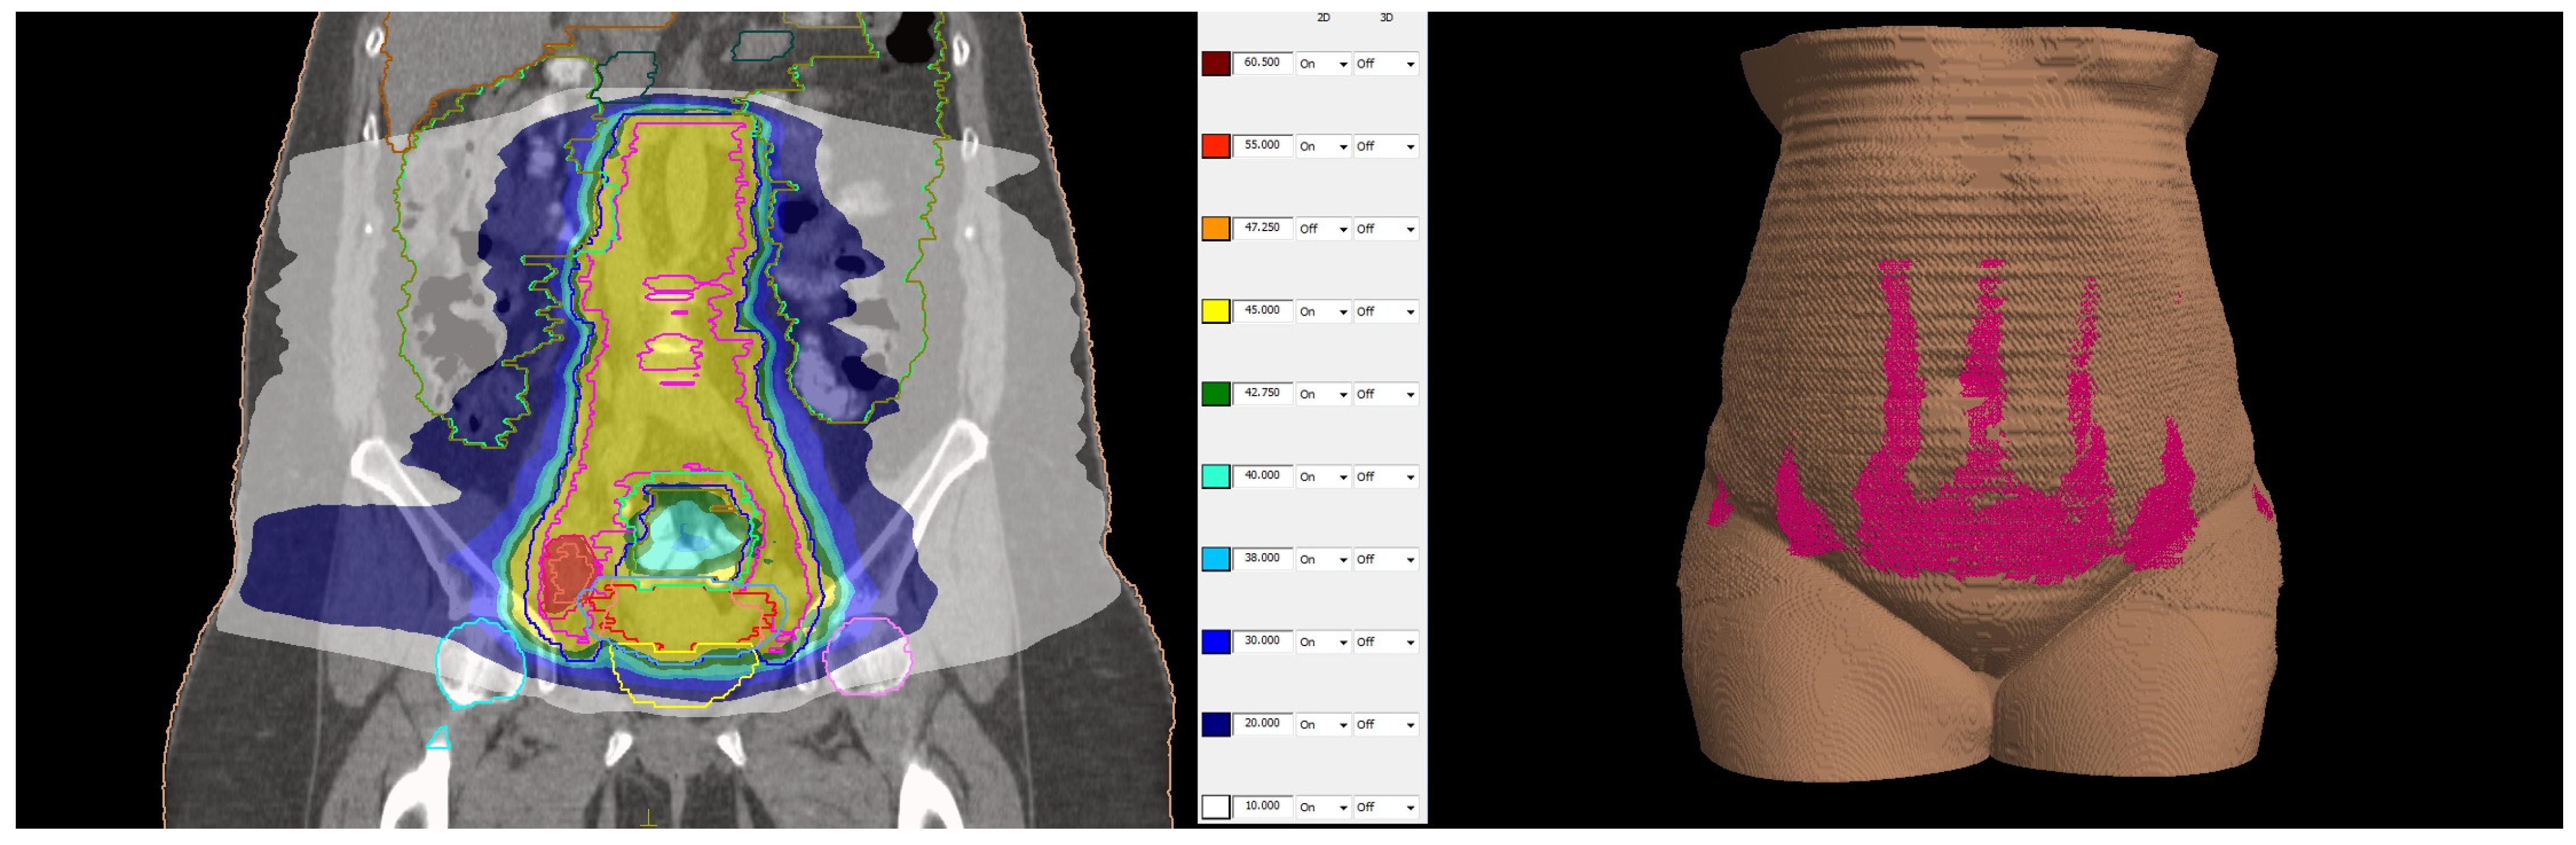

The patient was simulated in a prone position with hands above the head and was immobilized with a thermoplastic mask covering the abdominal and pelvic area. Knee and feet rests were also used for immobilization. Treatment planning computed tomography (CT) protocol included oral administration of 50 mL iodine contrast media in 500 mL of water 30 min before simulation and CT images with 2 mm slice thickness. The treatment planning system (TPS) Monaco 5.1. was used for dosimetric calculation. The contoured organs at risk (OAR) included the small bowel, liver, spleen, pancreas, stomach, spinal cord, kidneys, bladder, rectum, sigmoid colon, skin, and femoral heads and necks. The clinical target volume (CTV) included the uterine body, cervix and parametria, the upper vaginal third, and regional lymph nodes: common, internal, and external iliac, obturator, presacral, and paraaortic up to the renal vessels. The prescribed dose to the planned target volume (PTV) was 45 Gy in 25 fractions, five times a week, with a CTV to PTV margin of 5 mm. The involved lymph nodes received a simultaneous integrated boost dose of 55 Gy in 25 fractions with a 3 mm safety margin from the gross tumor volume to the PTV. Dosimetric planning was performed using a single 360–arc with 6 MV photons. The achieved target coverage was as follows: 95% of the prescribed dose covered more than 95% of the PTVs, and 100% of the prescribed dose covered more than 99% of the CTVs. OARs met both the soft and hard constraints from the EMBRACE II protocol [15] except for the bowel and sigmoid colon, where only the soft constraints were achieved. In this particular case, additional actions were necessary during dosimetric planning to ensure the skin’s minimal radiation exposure. To evaluate skin dose, a structure covering the outer 5 mm of the body surface was created. The maximal skin dose was 34.09 Gy, with 30 Gy in 1.06 cm3, 20 Gy in 53.32 cm3, and 10 Gy in 552.84 cm3 (11.8% of the structure’s total volume). The maximal dose to the pubic skin was 12 Gy. The total and skin dose distributions are represented in Figure 3.

Figure 3.

(Left side): dose distribution from 55 Gy, which is 100% of the prescribed dose (in red) in boosted lymph nodes and 45 Gy (in yellow) prescribed dose in the whole PTV to 10 Gy (in white). (Right side): Three-dimensional reconstruction of the patient’s skin with the distribution of 10 Gy in pink. All regions of existing skin lesions were avoided and received less than 10 Gy.